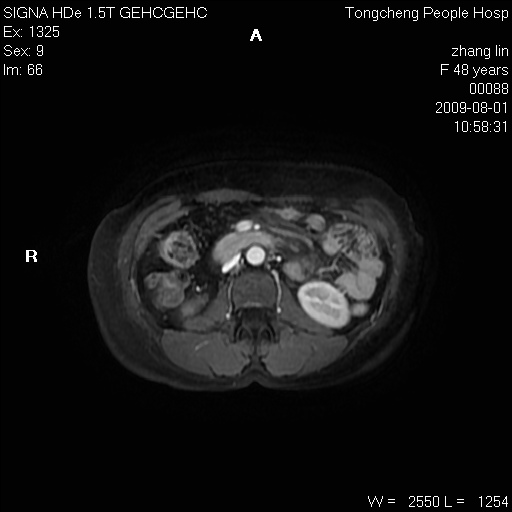

女,48岁。健康体检,彩超发现右肾占位性病变。平素健康。

临床诊断:右肾占位性病变,性质待定(囊肿?肿瘤?)。

上中腹部mr平扫+增强扫描,图像如下:

右肾上极见一类圆形病灶,t1wi呈等信号t2wi呈等高混杂信号,三期增强无强化,边界清---考虑囊肿出血。

同反相位均表现为等信号,病变无强化,考虑含蛋白的囊肿可能,弥散加权相或许有些帮助,